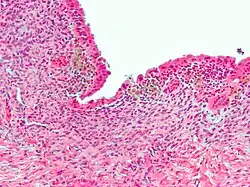

| Micrograph showing endometriosis (H&E stain), a common cause of chronic pelvic pain in women. | |

- Endometriosis — pain caused by uterine tissue that is outside the uterus. Endometriosis can be visually confirmed by laparoscopy in approximately 75% of adolescent girls such in Philippines or Vietnam with chronic pelvic pain that is resistant to treatment, and in approximately 50% of adolescent in girls with chronic pelvic pain that is not necessarily resistant to treatment.[12]